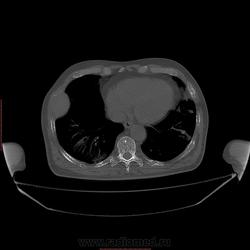

Пациент 1946 г.р., состоит на Д учете в онкодиспансере по поводу с-ч кожи (базалиома), прошел курс лучевой терапии, в 2009г на Ргенографии выявили образование 7 ребра, направили на Кт, на КТ (2009г) был выставлен д-з ГКО, пункционная биопсия не произведена. А сейчас вот такая картина, с множественными литическими очагами в костях грудного склета + образование 7 ребра, с отрицательной динамикой.

повторно взяли пациента, сняли кости таза, такая же картина- множественные очаги литической деструкции. Заключение: больше данных за миеломную болезнь.